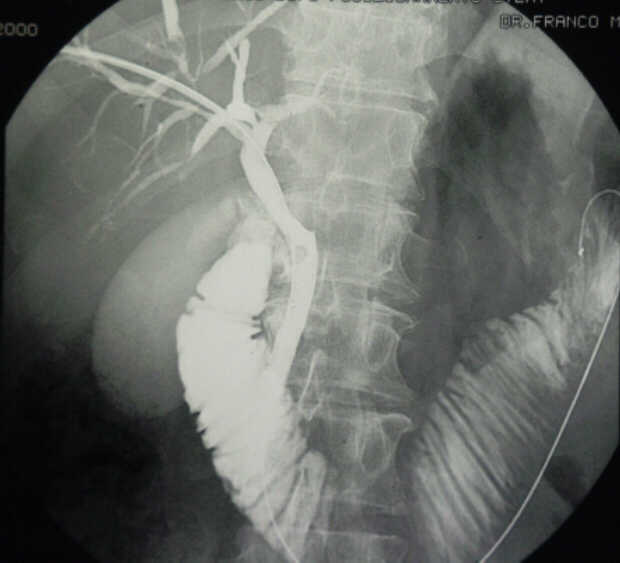

Pancreatic Head Mass: What Can Be Done?

Diagnosis: Angiography